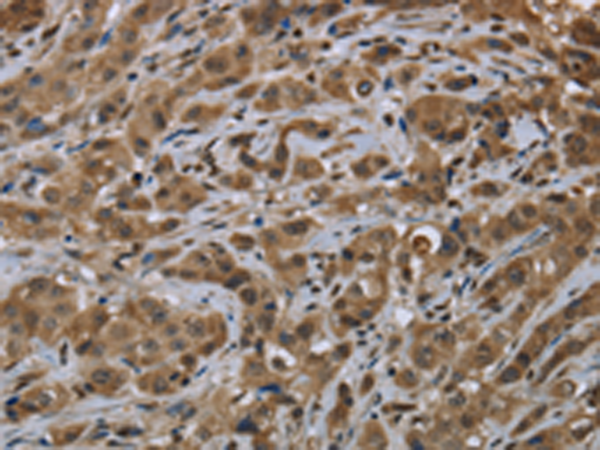

分类: 科研抗体货号: P01408别名: GLIPR; RTVP1; CRISP7应用: WB,IHC反应种属: Human, Mouse